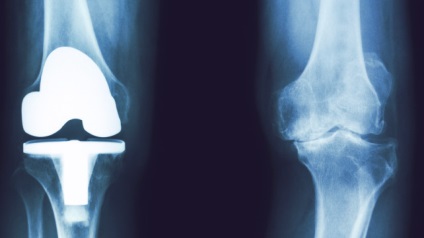

Ahhoz, hogy a megfelelő látható a teljes hiánya a közös tér, a bal oldalon látunk egy sor belső protézis, amely mentesíti a beteget a fájdalom.

Példa behelyezve csípöímplantátum. Az is látható, hogy a bal közös már van egy átlagos mértéke coxarthrosis.